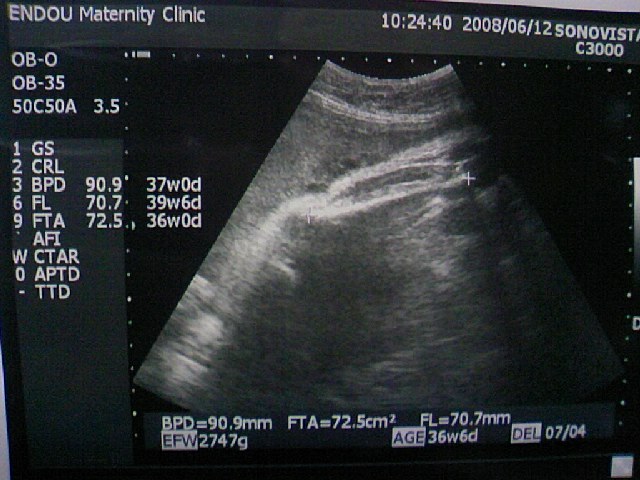

午前中、10ヶ月に入って初の検診に行ってきました!

←足のすねを測ってもらってるところ。

どーやらもう顔は見せてもらえない・・・

生まれてからのお楽しみですねw

<超音波検査>

推定体重 : 二週間前の前回2200g→2800gに増加! (+600g)